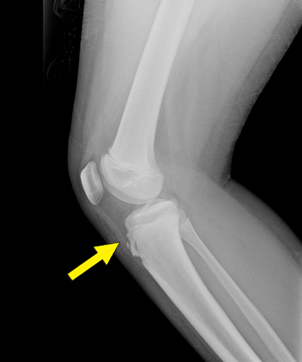

오른쪽 무릎에 나타난 오스굿슐라터병의 단순방사선촬영

진단/검사

병력청취와 단순 방사선촬영 검사로 진단한다. 단순 방사선촬영 검사를 해 보면 튀어나온 부분에 뼈 조각이 떨어져 있는 것이 보이기도 한다.